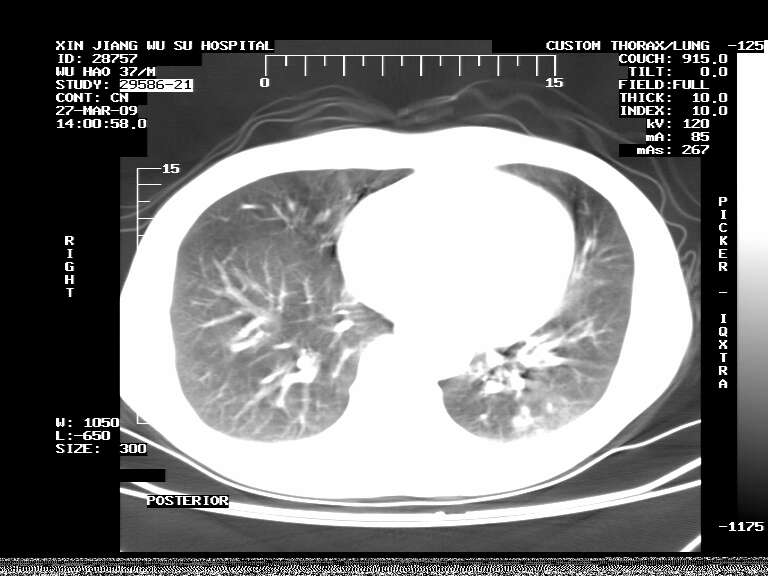

男,37岁,体检胸透发现阴影。

患者体检发现 无症状 左肺下叶占位,边缘模糊,可见血管聚束、分叶、胸膜牵拉,增强呈不均匀性强化。 首先考虑左肺下叶周围型肺癌,建议穿刺活检。

患者体检发现 无症状 左肺下叶占位,边缘模糊,可见血管聚束、分叶、胸膜牵拉,增强呈不均匀性强化。 首先考虑左肺下叶周围型肺癌,建议穿刺活检。支持!

左肺下叶见一结节病变,边缘欠清不光滑,与胸膜粘连且胸膜局限性增厚,注药后呈环形强化,动脉期壁呈明显点环状强化,静脉期壁强化减低,中心密度低无强化,灶周无明显的卫星灶和水肿区(晕征)---考虑周围性肺癌,不除外感染性病变,建议穿刺活检。

左肺下叶软组织病灶,密度较高,内见点状钙化,其周围见子灶,邻近胸膜扁平样增厚.c+病灶强化明显,中心强化弱.诊断:左肺下叶结核瘤.

周围有卫星灶,胸膜反应不明显,病灶中心有坏死。建议先抗结核治疗后,短期复查

左肺下叶大片实变影,内靠胸膜见不规则更高密度结节灶,边缘强化,相邻胸膜增厚,胸膜下脂肪线存在。考虑炎症,结核可能。